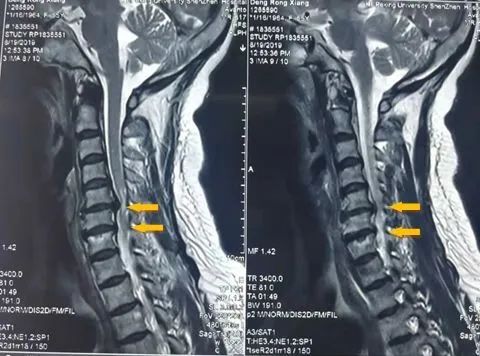

下肢症状 下肢症状出现早,而且较重,主要表现为缓慢进行性的双下肢麻木、发冷、疼痛、僵硬发抖、行走不稳、步态笨拙及无力等。经常打软腿,易绊倒,有的患者有行走踩棉花感、头重脚轻,步履蹒跚;严重者下肢痉挛、行路困难、卧床不起、生活不能自理。 上肢症状 出现较晚,某些较轻的或较早期的病人可能没有上肢症状,或症状被病人忽视。症状多为双侧上肢的感觉运动障碍,如:麻木、酸胀、烧灼感、疼痛发抖、无力以及活动不灵活等;甚至不能用手执笔、握筷子、端碗、系扣子等双手的精细动作。 由于脊髓型颈椎病往往同时合并神经根的损害,也就是出现神经根型颈椎病的部分症状。因此,病人可出现上肢的疼痛及麻木,症状可发生在一个或多个手指,手的桡侧(拇指侧)或尺侧(小指侧)的几个手指,也有在肩部、上臂和前臂者,也可有沿神经走行方向放射的。 躯干症状 胸腹部麻木、疼痛、身上如有紧带子捆绑的感觉,以致感到胸闷憋气不适。 骶神经症状 膀胱、直肠括约肌障碍也较常见,表现为尿急,一有想排尿的感觉时便急不可耐,有时排尿控制不好,甚至可以尿裤子。排尿无力、尿不尽感以及便秘等,严重者小便潴留或小便失禁。部分男性病人还可以有性功能障碍。 头部症状 脊髓颈椎病的症状的头部症状主要表现于头部异常疼痛、头晕和头皮麻痛。 发病机理 脊髓型颈椎病的基本病因是颈椎退变。在颈椎各个结构中,颈椎间盘退变被认为发生最早。随着椎间盘质地变性,含水量减少,高度下降和周缘突出,椎间盘后部被覆的后纵韧带的增厚骨化,椎体边缘骨质增生,相应椎板间黄韧带及椎间关节应力增加,韧带关节囊增厚,弹性减少,造成椎管径线减少,尤其是前后径,即矢状径的减少构成了脊髓压迫症的静态因素。 动态性因素主要是指颈椎的伸屈活动加重脊髓的应力、变形。颈椎伸展时,椎管长度缩短,脊髓松弛,脊髓组织变“短粗”,截面积增大,黄韧带自侧后方折入椎管,纤维环及被覆的后纵韧带后突,脊髓受压增加;颈椎屈曲时,椎管拉长,脊髓变扁、变宽,弓弦作用使其前移,椎管前方之骨赘和突出的椎间盘组织抵压脊髓,加重脊髓损害。颈椎后伸时,为上一椎体后下缘与下一椎节椎弓后部前上缘靠拢,产生对脊髓“钳压”作用,特别是在原有椎管狭窄的情况下,这种作用更加明显。 鉴别诊断 本型颈椎病虽较为少见但症状严重,且多以隐性侵袭的形式发展,易误诊为其他疾患而延误治疗时机,因此其在诸型颈椎病中处于重要地位。由于其主要压迫或刺激脊髓及伴行血管而出现脊髓神经的感觉、运动、反射与排便功能障碍故称之为脊髓型颈椎病。很多患者多没有认识到该病的严重性,有的患者由于失治、误治导致严重的后果,甚至瘫痪。应引起足够重视,其鉴别诊断尤为重要。 脊髓肿瘤 病人有颈、肩、臂、手指的疼痛或麻木,同侧上肢为下运动神经元的损伤,下肢为上运动神经元的损伤。症状逐渐发展到对侧下肢,最后到达对侧上肢。压迫平面以下感觉减退及运动障碍的情况开始为Brown Sequard综合征,最后发展为脊髓横贯性损害现象。 其特点是:①X线平片显示椎间孔增大、椎体或椎弓破坏。②脊髓碘油造影,梗阻部位造影呈倒杯状,脊椎穿刺Queckenstedt试验阴性。③在完全梗阻病例,脑脊液呈黄色,易凝固,蛋白含量增高。 后纵韧带骨化症 因为后纵韧带的骨化使椎管狭窄,影响脊髓血液循环。严重者可以压迫脊髓引起瘫痪。脊髓造影和CT及核磁共振对其诊断有很大的帮助。 枕骨大孔区肿瘤 其症状是枕后痛,同侧上肢痉挛性麻痹,并发展到下肢、同侧下肢和对侧上肢。手和前臂肌肉有萎缩现象。有时可出现感觉改变。其特点是:①脊髓造影,梗阻的位置较高,碘油难以到达颅腔。②可出现颅凹脑神经的症状。③晚期可引起脑压升高,有眼底水肿、脑膜刺激征。 脊髓粘连性蛛网膜炎 其表现为脊神经感觉根(前根)和运动根(后根)的神经症状,或有脊髓的传导束症状。Queeckenstedt试验有不全梗阻或完全梗阻。细胞数及蛋白的增加无一定数值。其特点是:脊髓造影时,碘油通过蛛网膜下腔时困难,呈蜡泪状变化。 脊髓空洞症 1)概述:本病与延髓空洞症均属慢性退行性病变,以髓内空洞形成及胶质增生为特点,其病程进展缓慢,早期影响上肢呈节段性分布,当空洞逐渐扩大时,由于压力或胶质增生不断加重,可使脊髓白质内的长传导束也被累及本病,临床上易与脊髓型颈椎病混淆。好发于颈胸段,有时感到臂部疼痛。其特点是:①发生于年轻人,多为20~30岁。②痛觉与其它深浅感觉分离,以温度觉减退或消失为明显。 2)鉴别要点: 感觉障碍:本病早期为一侧性痛觉及温度感觉障碍,当病变波及前连合时,则可有双侧手部、前臂尺侧及部分颈、胸部的痛温觉丧失,而触觉及深感觉则基本正常,此现象称为感觉分离性障碍。颈椎病患者则无此种现象。 营养性障碍:由于痛觉障碍不仅可在局部引起溃疡烫伤,皮下组织增厚及排汗功能障碍等病变,且可在关节处引起过度的增生及磨损性改变甚至出现超限活动而无痛感,此称为夏科关节。应注意与因脊髓痨所致者鉴别。 原发性侧索硬化症 这是一种原因不明的神经系统疾病,当侵犯皮层脊髓运动束时,表现为双侧锥体束损伤,肌张力增高,浅反射消失,肌肉萎缩。 其特点是:①无感觉障碍;②Queckenstedt试验通畅;③脊髓造影无阻塞现象。其运动神经元变性仅限于上运动神经元而不波及下运动神经元,较前者为少见,主要表现为进行性、强直性截瘫或四肢瘫无感觉及膀胱症状如病变波及皮质延髓束时,则可出现假性延髓性麻痹(假性球麻痹)征象。 肌萎缩性侧索硬化症 1)概述:本病属于运动神经元疾患中的一种类型,是一种原因不明的脑干运动核、皮层脊髓束和脊髓前角细胞损害的疾病。其病因至今尚不明了。发病缓慢,好发于中年人的颈膨大部。在临床上主要引起以上肢症状重于下肢的四肢性瘫痪,因此易与脊髓型颈椎病相混淆。 本病目前尚无有效的疗法,预后差,手术可加重病情或引起死亡;而脊髓型颈椎病患者则需及早施术,故两者必须加以鉴别,以明确诊断及选择相应的治疗方法:①上肢肌肉萎缩性瘫痪,小肌肉明显,手呈鹰爪形。②下肢痉挛性瘫痪,腱反射活跃或亢进。③病变发展到脑干时,可发生延髓麻痹而死亡。 2)鉴别要点: 年龄特点:脊髓型颈椎病患者多在45~50岁以上,而本病发病年龄较早,常在40岁前后起病年轻者甚至30岁左右。 感觉障碍:本病一般均无感觉障碍,仅部分病例可有感觉异常主诉;而在颈椎病患者当引起脊髓受压出现运动障碍时,则均伴有感觉障碍症状与体征。 起病速度:颈椎病发病较慢且多伴有一定诱因;而本病则多无任何原因突然发病,常先从肌无力开始,且病情发展快 。 肌萎缩情况:本病虽可发生于身体任何部位,但以上肢先发者为多尤以手部小肌肉明显。大小鱼际肌和蚓状肌萎缩,掌骨间隙凹陷,双手可呈鹰爪状并迅速向前臂肘部及肩部发展,甚至引起颈部肌肉无力与萎缩,故对此类病例应常规检查胸锁乳突肌、肩胛提肌及颈部肌群以判定有无萎缩征。而颈椎病由于以颈5~6、颈6~7及颈4~5处多见,故肌肉受累水平罕有超过肩部以上者。 自主神经症状:本病少有出现此症状者而在脊髓型颈椎病患者常可遇到。 发音障碍:当侧索硬化波及延髓时(可在起病时出现但多见于本病的后期)可出现发音含糊渐而影响咀嚼肌及吞咽动作,而脊髓型颈椎病患者则无此症状,只有当病变波及椎动脉时方有轻度发音障碍。 椎管矢状径:本病时多属正常,而脊髓型颈椎病患者则显示较明显的狭窄征。 脑脊液检查:颈椎病患者多有不完全性阻塞及脑脊液生化检查异常等,而本病时则多属正常。 脊髓造影:本病均属阴性,而颈椎病患者则有阳性所见。 其他:包括本病各期所特有的肌电图征、肌肉活组织检查以及CT和MRI检查等均有助于本病与脊髓型颈椎病的鉴别诊断。 本病的预后较差,目前尚无有效措施阻止本病的进展,多在起病后数年至十余年死于各种并发症或呼吸障碍。 共济失调症 本病多有明显的遗传性,视其病变特点不同而分为少年脊髓型共济失调(又名Friedreich共济失调症)、脊小脑型共济失调、小脑型共济失调及周围型共济失调等数种且亚型较多。 本病不难与脊髓型颈椎病鉴别,关键是对本病要有一个明确认识,在对患者查体时应注意有无肢体共济失调、眼球震颤及肢体肌张力低下等症状阳性结果有助于对本病的判定。 颅底凹陷症 1)概述:近年来发现本病并非罕见因无特效疗法,病员常求治于各医院门诊之间。由于其可引起脊髓压迫症状,因此应与脊髓型颈椎病加以鉴别。 2)鉴别要点:主要依据:本病属先天畸形,具有其固有的临床特点: 短颈外观:主要因上颈椎凹入颅内所致。 标志测量异常:临床常采用的为以下两种: A.颅底角:指蝶鞍和斜坡所形成的角度取颅骨侧位片测量之正常为132°,如超过145°则属扁平颅底。 B.硬腭-枕大孔线:又名Chamberlain线,即硬腭后缘至枕大孔后上缘的连线在正常情况下,枢椎的齿突顶端低于此线如高于此线则属扁平颅底。 其他:本病患者发病年龄多较早,可在20~30岁开始发病;临床上多表现为四肢痉挛性瘫痪,且其部位较脊髓型颈椎病患者为高程度较重;多伴有疼痛性斜颈畸形及颈椎骨骼其他畸形;病程后期如引起颅内压增高,则可出现颅内症状。 多发性硬化症 1)概述:本病为一种病因尚不十分明了的中枢神经脱髓鞘疾患,因可出现锥体束症状及感觉障碍而易与脊髓型颈椎病相混淆。 本病虽在国内少见但也非罕见,其可引起与脊髓型颈椎病相类同的感觉障碍及肢体痉挛性瘫痪,故在诊断上应想及此病。本病尚无特效疗法手术可加剧病情甚至引起意外,因此切忌误诊。 2)鉴别要点:主要依据以下五点进行鉴别: 好发年龄:多在20~40岁之间,女性多于男性。 精神症状:多有程度不同的精神症状,常呈欣快状情绪易冲动。 发音障碍:病变波及小脑者可出现发音不清甚至声带瘫痪。 脑神经症状:以视神经受累为多,其他脑神经亦可波及。 共济失调症状:当病变波及小脑时可出现。 周围神经炎 1)概述:本病系由于中毒感染及感染后的变态反应等所引起的周围神经病变,主要表现为对称性或非对称性(少见)的肢体运动、感觉及自主神经功能障碍。可单发或多发,其中因病毒感染或自体免疫功能低下而急性发病者,称为急性多发性神经根炎(Guillain Barre症候群)。 2)鉴别要点:主要依据本病的对称性症状特点,包括: 对称性运动障碍:通常表现为以四肢远端为重的对称性弛缓性、不完全性瘫痪,此不同于颈椎病时的不对称性痉挛性瘫痪。 对称性感觉障碍:可出现上肢或下肢双侧对称性似手套-袜子型感觉减退,颈椎病患者亦罕有此种改变。 对称性自主神经功能障碍:主要表现为手足血管舒缩出汗和营养性改变。 根据以上三点不难与脊髓型颈椎病区别此外,尚可参考病史X线片、MRI及CT等其他有关检查。非病情特别需要一般勿需脊髓造影。 继发性粘连性脊蛛网膜炎 1)概述:近年来发现本病日渐增多除由于外伤、脊髓与脊神经根长期遭受压迫所致外,大多系因椎管穿刺、椎管内或椎管外注药、蛛网膜下隙阻滞及脊髓造影等所引起,因此,大多属于医源性因素本病可与颈椎病伴发亦可单独存在。 2)鉴别要点: 病史:既往多有椎管穿刺、注药或脊髓造影等病史,尤其是某些刺激性较大的造影剂(目前已不再为大家所选用)更易引起。 根性刺激症状:多较明显,尤其是病程较长者常表现为根性痛其范围多较广泛,且呈持续性可有缓解期,但在增加腹压时加剧。 影像学改变:既往曾行碘油造影者在X线平片上显示椎管内有烛泪状阴影,多散布于两侧根袖处。此外,MRI技术可以较清晰地显示蛛网膜下隙粘连的范围与程度,有助于与脊髓型颈椎病者的鉴别,但有不少病例两者同时伴发。 颈髓过伸性损伤 1)概述:颈髓过伸性损伤又名脊髓中央管症候群属于颈部外伤中的一种类型,临床易与在颈椎病基础上遭受过屈损伤所造成的脊髓前中央动脉症候群相混淆前者大多需要先采用保守疗法,后者则需及早施术,故对两者的鉴别具有现实意义。 2)鉴别要点: 损伤机制:两者均发病于头颈部外伤后,过伸性损伤者大多因高速行驶的车辆急刹车所引起,由于惯性的作用,乘客面颌、颏部遭受正前方的撞击,使头颈向后过度仰伸;此时已被拉长的脊髓(椎管亦变得相对狭窄)易突然被嵌夹于前突内陷的黄韧带与前方骨纤维性管壁之中引起脊髓中央管周围损害而脊髓前中央动脉症候群患者则多系在椎体后缘骨刺或髓核突出的基础上,突然遭受使头颈前屈的暴力所致以致脊髓前方被撞击到骨性或软骨性致压物上引起脊髓前中央动脉的痉挛与狭窄,并出现供血不全症状。 运动障碍:由于过伸性损伤的病理改变位于脊髓中央管周围,因此最先累及上肢的神经传导束而先出现上肢瘫痪,或是上肢重下肢轻,尤以手部最为明显而脊髓前中央动脉症候群患者则完全相反,其瘫痪是以下肢重而上肢轻。 感觉障碍:脊髓前中央动脉症候群患者感觉功能受累较轻。而过伸性损伤患者不仅症状明显,且可出现感觉分离现象即温痛觉消失,而位置觉、深感觉存在,此主要是由于病变位于中央管附近所致。 影像学改变:X线平片上两者有明显差异过伸性损伤者在侧位观察可以发现患节椎间隙前方呈增宽状且椎体前阴影明显增宽多超过正常值1倍以上而脊髓前中央动脉症候群患者由于多在骨刺形成的基础上发病因此不仅多有骨赘存在,且椎管一般较狭窄(宽椎管者不易发病)。 其他:尚可参考面颌部或头后部有无软组织损伤,以及患者年龄及病史等加以区别。一般勿需脊髓造影。